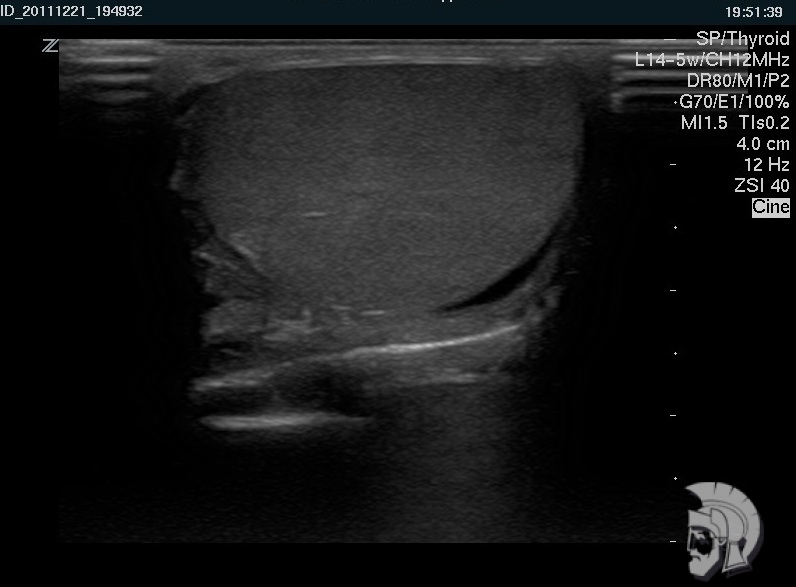

| Фото яичка. Нормальная эхо-структура яичка мужчины 35 лет |